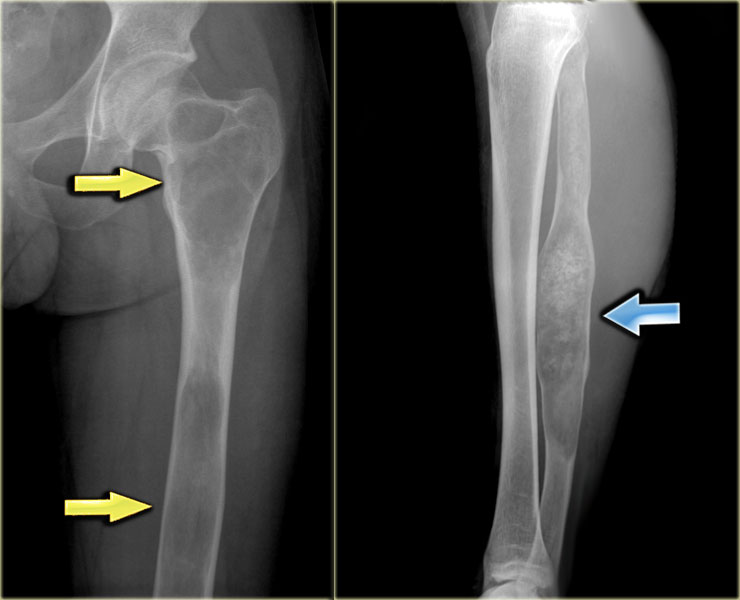

Eosinophilic granuloma (2)

Here some examples of EG demonstrating the various more or less aggressive presentations as ill-defined osteolytic lesions (blue arrow) and even as a less common sclerotic lesion (red arrow).

Eosinophilic granuloma (4)

On the left an ill-defined lytic lesion in the shaft of the femur with a solid layered periosteal reaction.

Differential diagnosis: EG, osteomyelitis and Ewing sarcoma.

Ewing sarcoma usually shows an irregular and interrupted periosteal reaction, however cannot be excluded.

Axial T2-WI with FS shows high SI of the bone marrow and a soft tissue mass envelopping the bone.